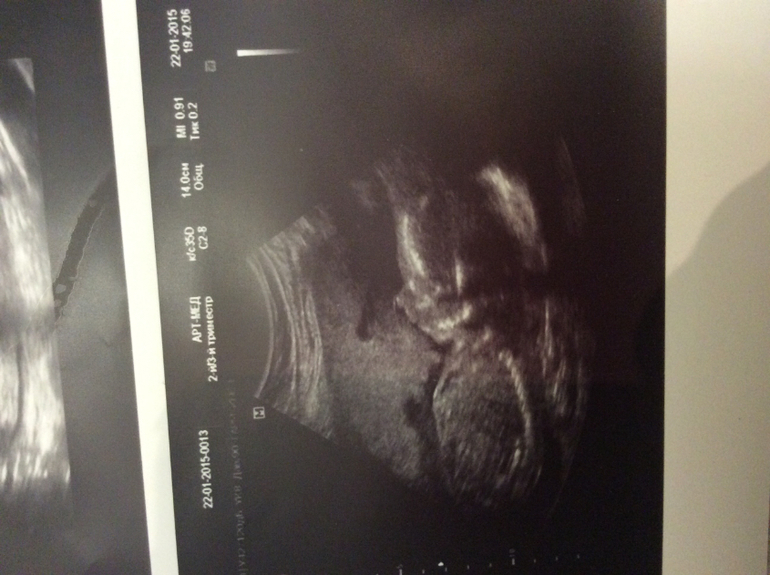

Всё о нашей беременностиДобрый вечер мои дорогие)! Вот отчитываясь , прошли второй скрининг .... С Артемкой все хорошо.... А вот мне почти постельный режим прописали ((((( шейка 32 но канал раскрытие немного.... Так что лежу .... От тонуса принимаю гинипрал( слава богу мне достали 15 упаковок) до конца хватит... Ну и фото сыночка и..............................,,,. Мужские прелести)))))))))!!!!!!